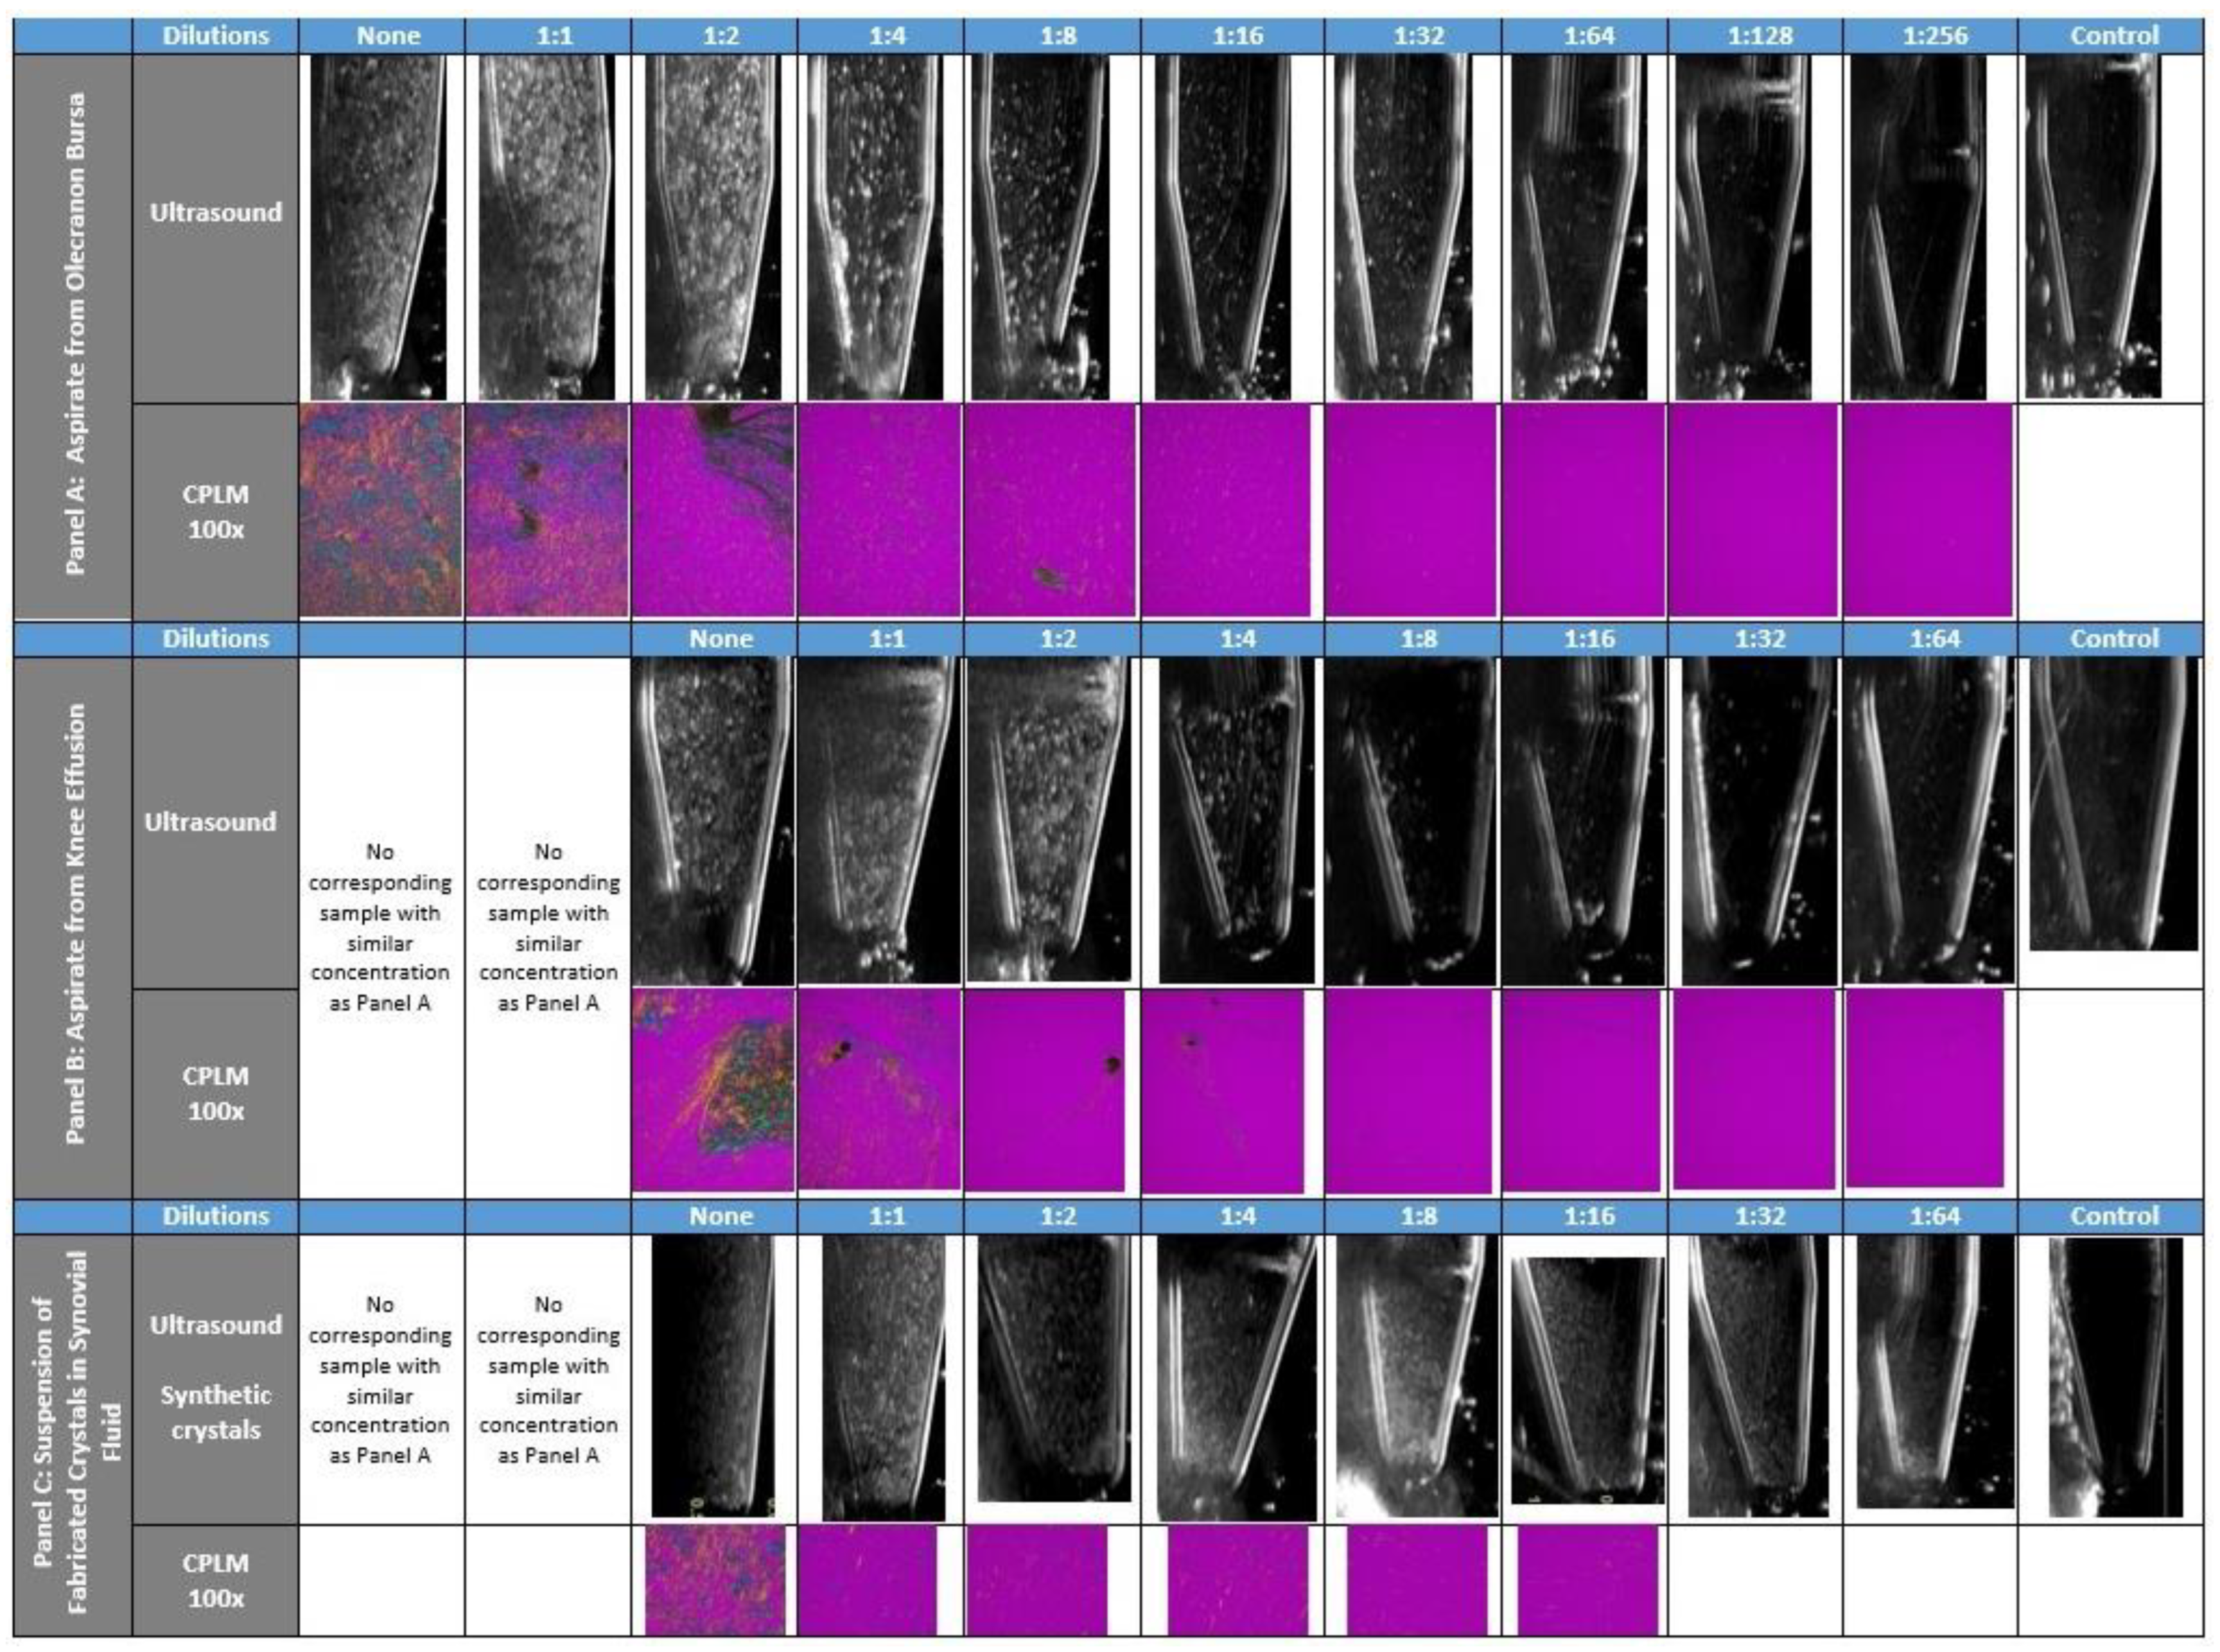

2.2. Ultrasound & CPLM Imaging

3. Results